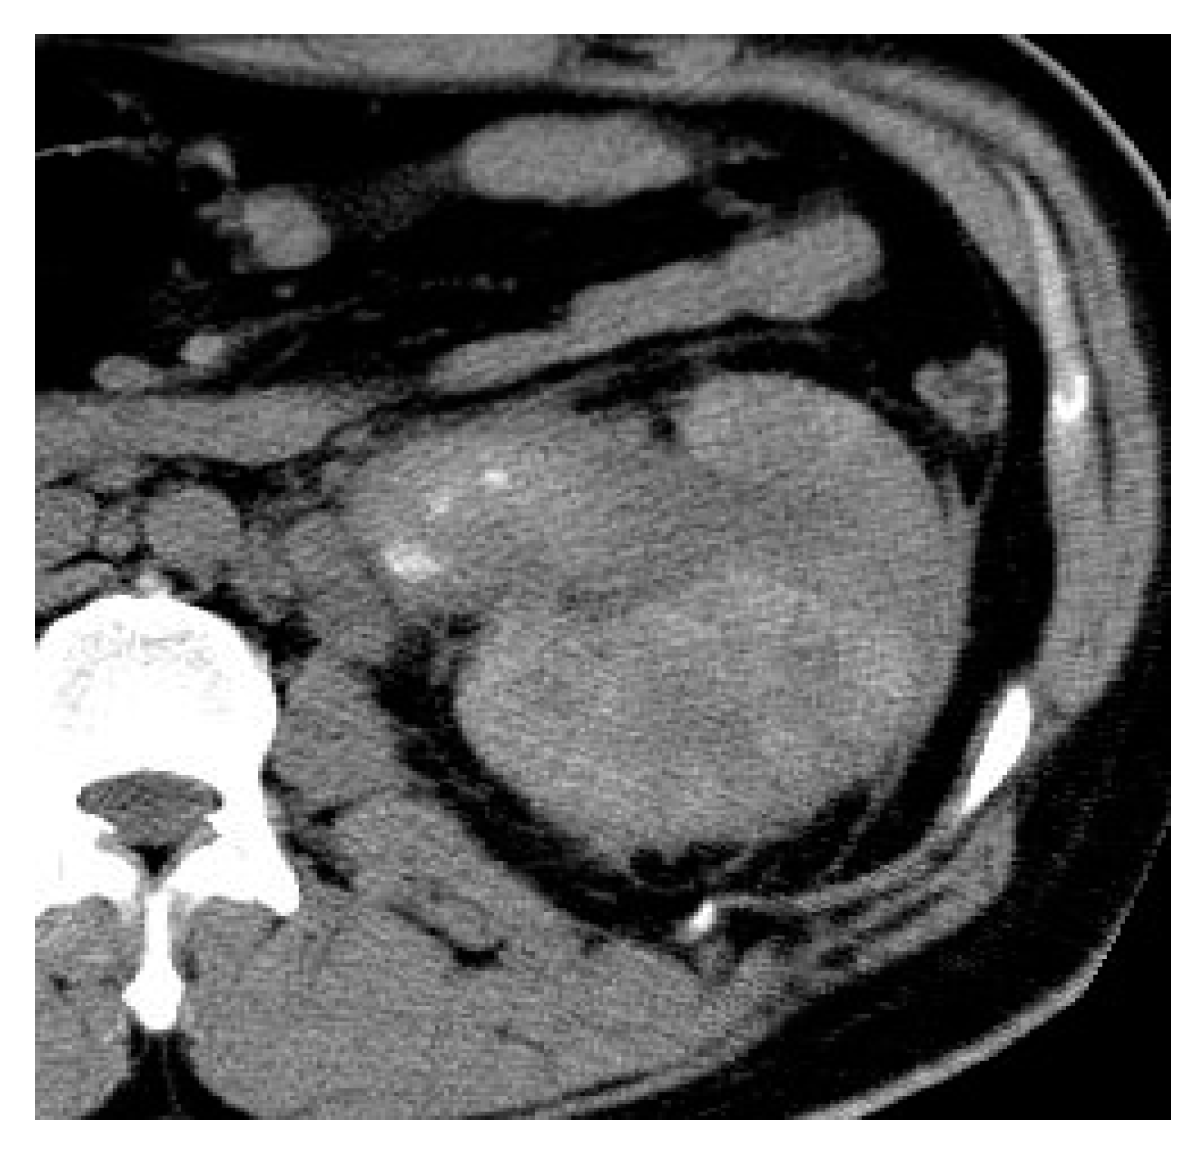

2.5. Xanthogranulomatous Pyelonephritis (XGP)

| Xanthogranulomatous Pyelonephritis | Non-functioning enlarged kidney, obstructing stone within a non-dilated renal pelvis, expansion of the calyces, and inflammatory changes in the perinephric fat. |